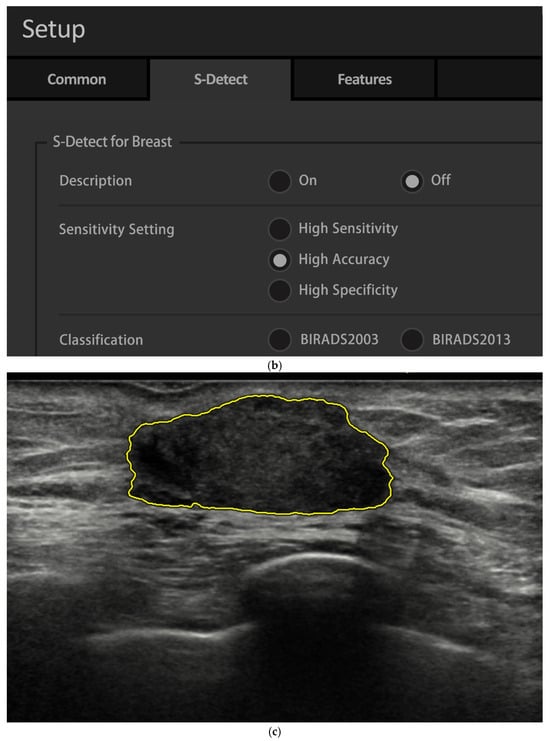

2.4. AI Analysis